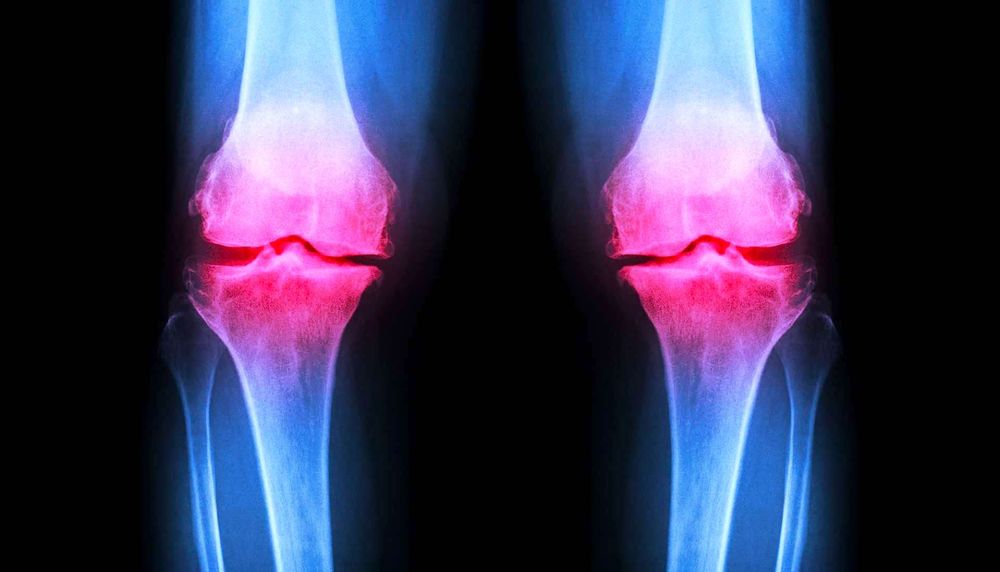

Un hydrogel injectable pour régénérer le cartilage endommagé des articulations

Suite à un accident, à une maladie ou au vieillissement naturel des articulations, le cartilage peut devenir irrémédiablement endommagé, engendrant douleurs et problèmes de mobilité. Un nouvel hydrogel pourrait considérablement améliorer le traitement des lésions cartilagineuses. Les propriétés uniques de ce gel, qui fournit un échafaudage sur lequel les cellules du cartilage se développent, permettent de l'implanter par une simple chirurgie en trou de serrure.

Le traitement des lésions du cartilage est difficile, car le tissu ne cicatrise pas bien, voire pas du tout, chez l'adulte. Il est possible d'essayer de réparer le cartilage en implantant des cellules cartilagineuses — généralement prélevées sur la personne traitée — pour régénérer les zones endommagées. Si cette technique est utilisée depuis 1987, elle se heurte à de nombreuses difficultés.

Les études sur les animaux portaient sur le traitement du cartilage articulaire endommagé, c'est-à-dire le cartilage qui recouvre l'extrémité des os. Cependant, de nombreuses blessures au genou impliquent des dommages au ménisque, le cartilage qui se trouve entre les os. D'autres études sur les animaux seraient nécessaires pour déterminer si la réparation du ménisque est possible, indique Lin. Le gel peut également être utilisé pour l'ingénierie tissulaire de la peau, et un essai clinique est déjà en cours. « Des résultats prometteurs ont été obtenus », dit-elle.